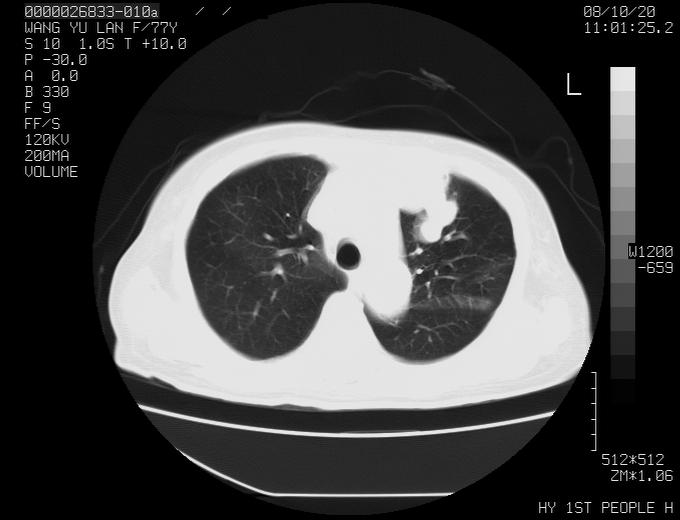

女性,77岁,胸部疼痛半月。左上肺团块影,本人考虑血管畸形,请分析

左上叶前段多发结节肿块并前段支气管息肉样结节、上叶腋亚段阻塞性肺炎,以结核可能性大。

纵隔有多个淋巴结肿大,提示周围型肺癌并转移可能性大。

左肺周围型肺癌并肺门淋巴结转移,很典型了!